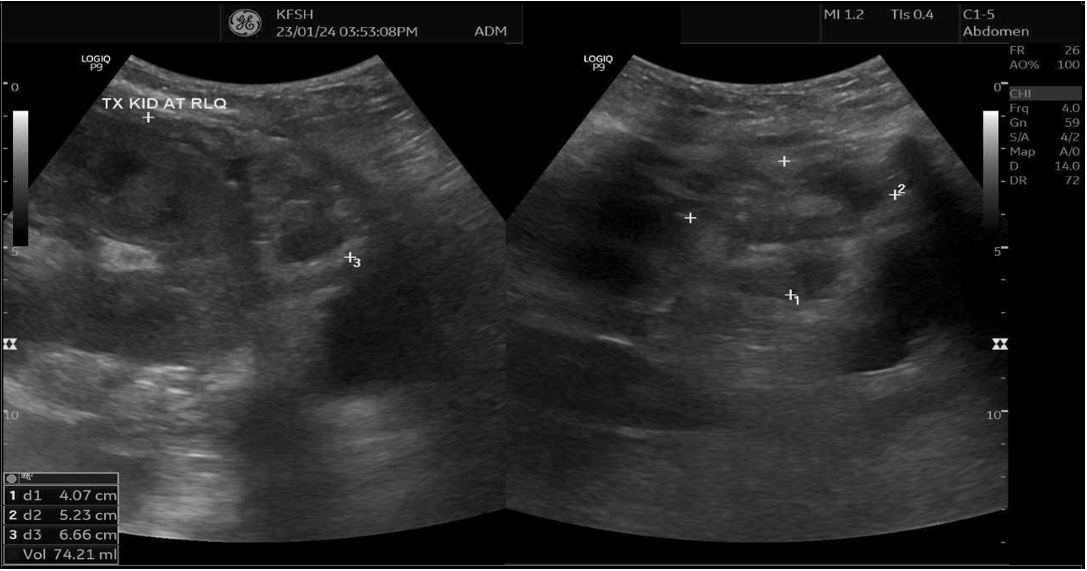

Upon presentation to our emergency department, her vital signs were notable for hypertension (BP 216/118 mmHg) and tachycardia (HR 109 bpm), though she remained afebrile and maintained oxygen saturation of 100%. Physical examination revealed ecchymosis over the right lower quadrant at the surgical site. Laboratory investigations showed severe anemia (Hb 7 g/dL), thrombocytopenia (66 × 10⁹/L), and serum creatinine (68 µmol/L). Abdominal ultrasound demonstrated preserved perfusion of the graft with patent main renal vessels. However, there was a significant increase in resistive index (RI) values within the intrarenal arterial branches, with areas showing a monophasic wave pattern, suggestive of impaired intrarenal flow and warranting close follow-up [Figure 1]. Additionally, elevated velocity at the main renal artery anastomosis site was noted, likely reflecting postoperative changes. A peri-graft fluid collection was identified, with the largest pocket measuring approximately 74 mL, requiring ongoing monitoring for potential complications.

Figure 1: Doppler showing elevated intrarenal resistive index with monophasic waveforms, suggesting impaired intrarenal flow (RI = 0.91).

Figure 2: (A) Ultrasound Doppler of renal transplant showing perigraft heterogeneous fluid collection measuring 4.0 × 5.2 × 6.6 cm (74 mL) (B) Left lower quadrant collection measuring 8.6 × 4.8 × 12 cm (267 mL).